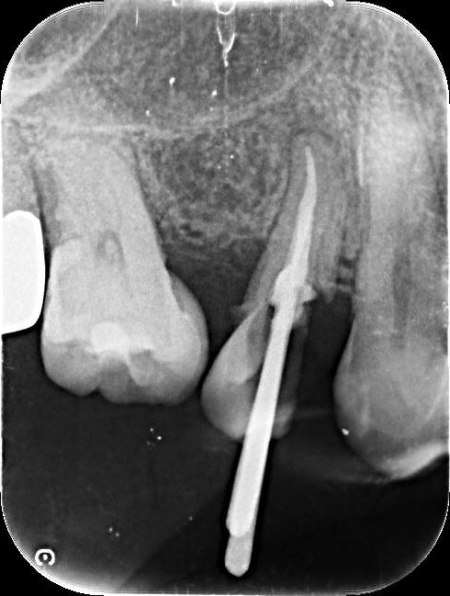

| 行ったご提案・治療内容 | 患者様は、歯をできるだけ残したいと希望されています。 そのため、感染した神経を取り除いて歯根内部を清掃・消毒する「根管治療」を行い、歯全体を覆う被せ物を装着する方法を提案し、同意いただきました。 メリット デメリット まず、根管治療で神経を慎重に取り除き、根管内の清掃と消毒を行います。 次に、歯を保護するための被せ物「ジルコニアクラウン」を装着します。 最後に、痛みや違和感がないか、問題なく噛むことができるかを確認し、治療を終了しています。 |

治療中